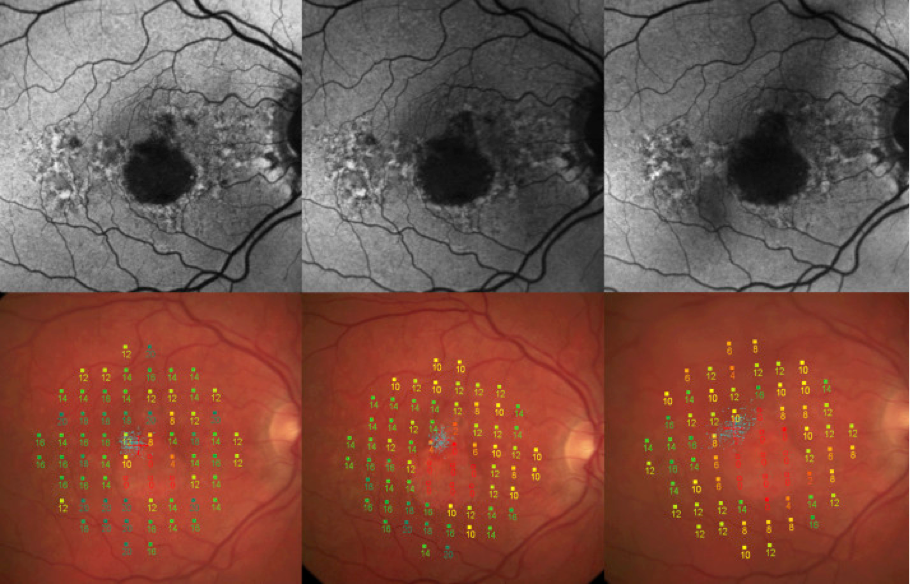

Mikroperimetrie

Mithilfe der Mikroperimetrie wird die Fähigkeit des Auges beurteilt, Lichtreize in verschiedenen Teilen der Netzhaut wahrzunehmen. Dabei handelt es sich um ein Gerät zur Darstellung der Netzhaut mithilfe eines Gesichtsfeld-Tests, mit dem die Funktion der Photorezeptoren räumlich dargestellt werden kann. Photorezeptoren sind die lichtempfindlichen Zellen in der Netzhaut. Bei der Mikroperimetrie wird die Netzhaut mit kleinen Lichtpunkten unterschiedlicher Intensität bestrahlt. Durch Drücken einer Taste bestätigt der Patient die Wahrnehmung des Lichtreizes.15 Mögliche Einschränkungen des Gesichtsfelds werden dann auf der Netzhaut der Person identifiziert.15